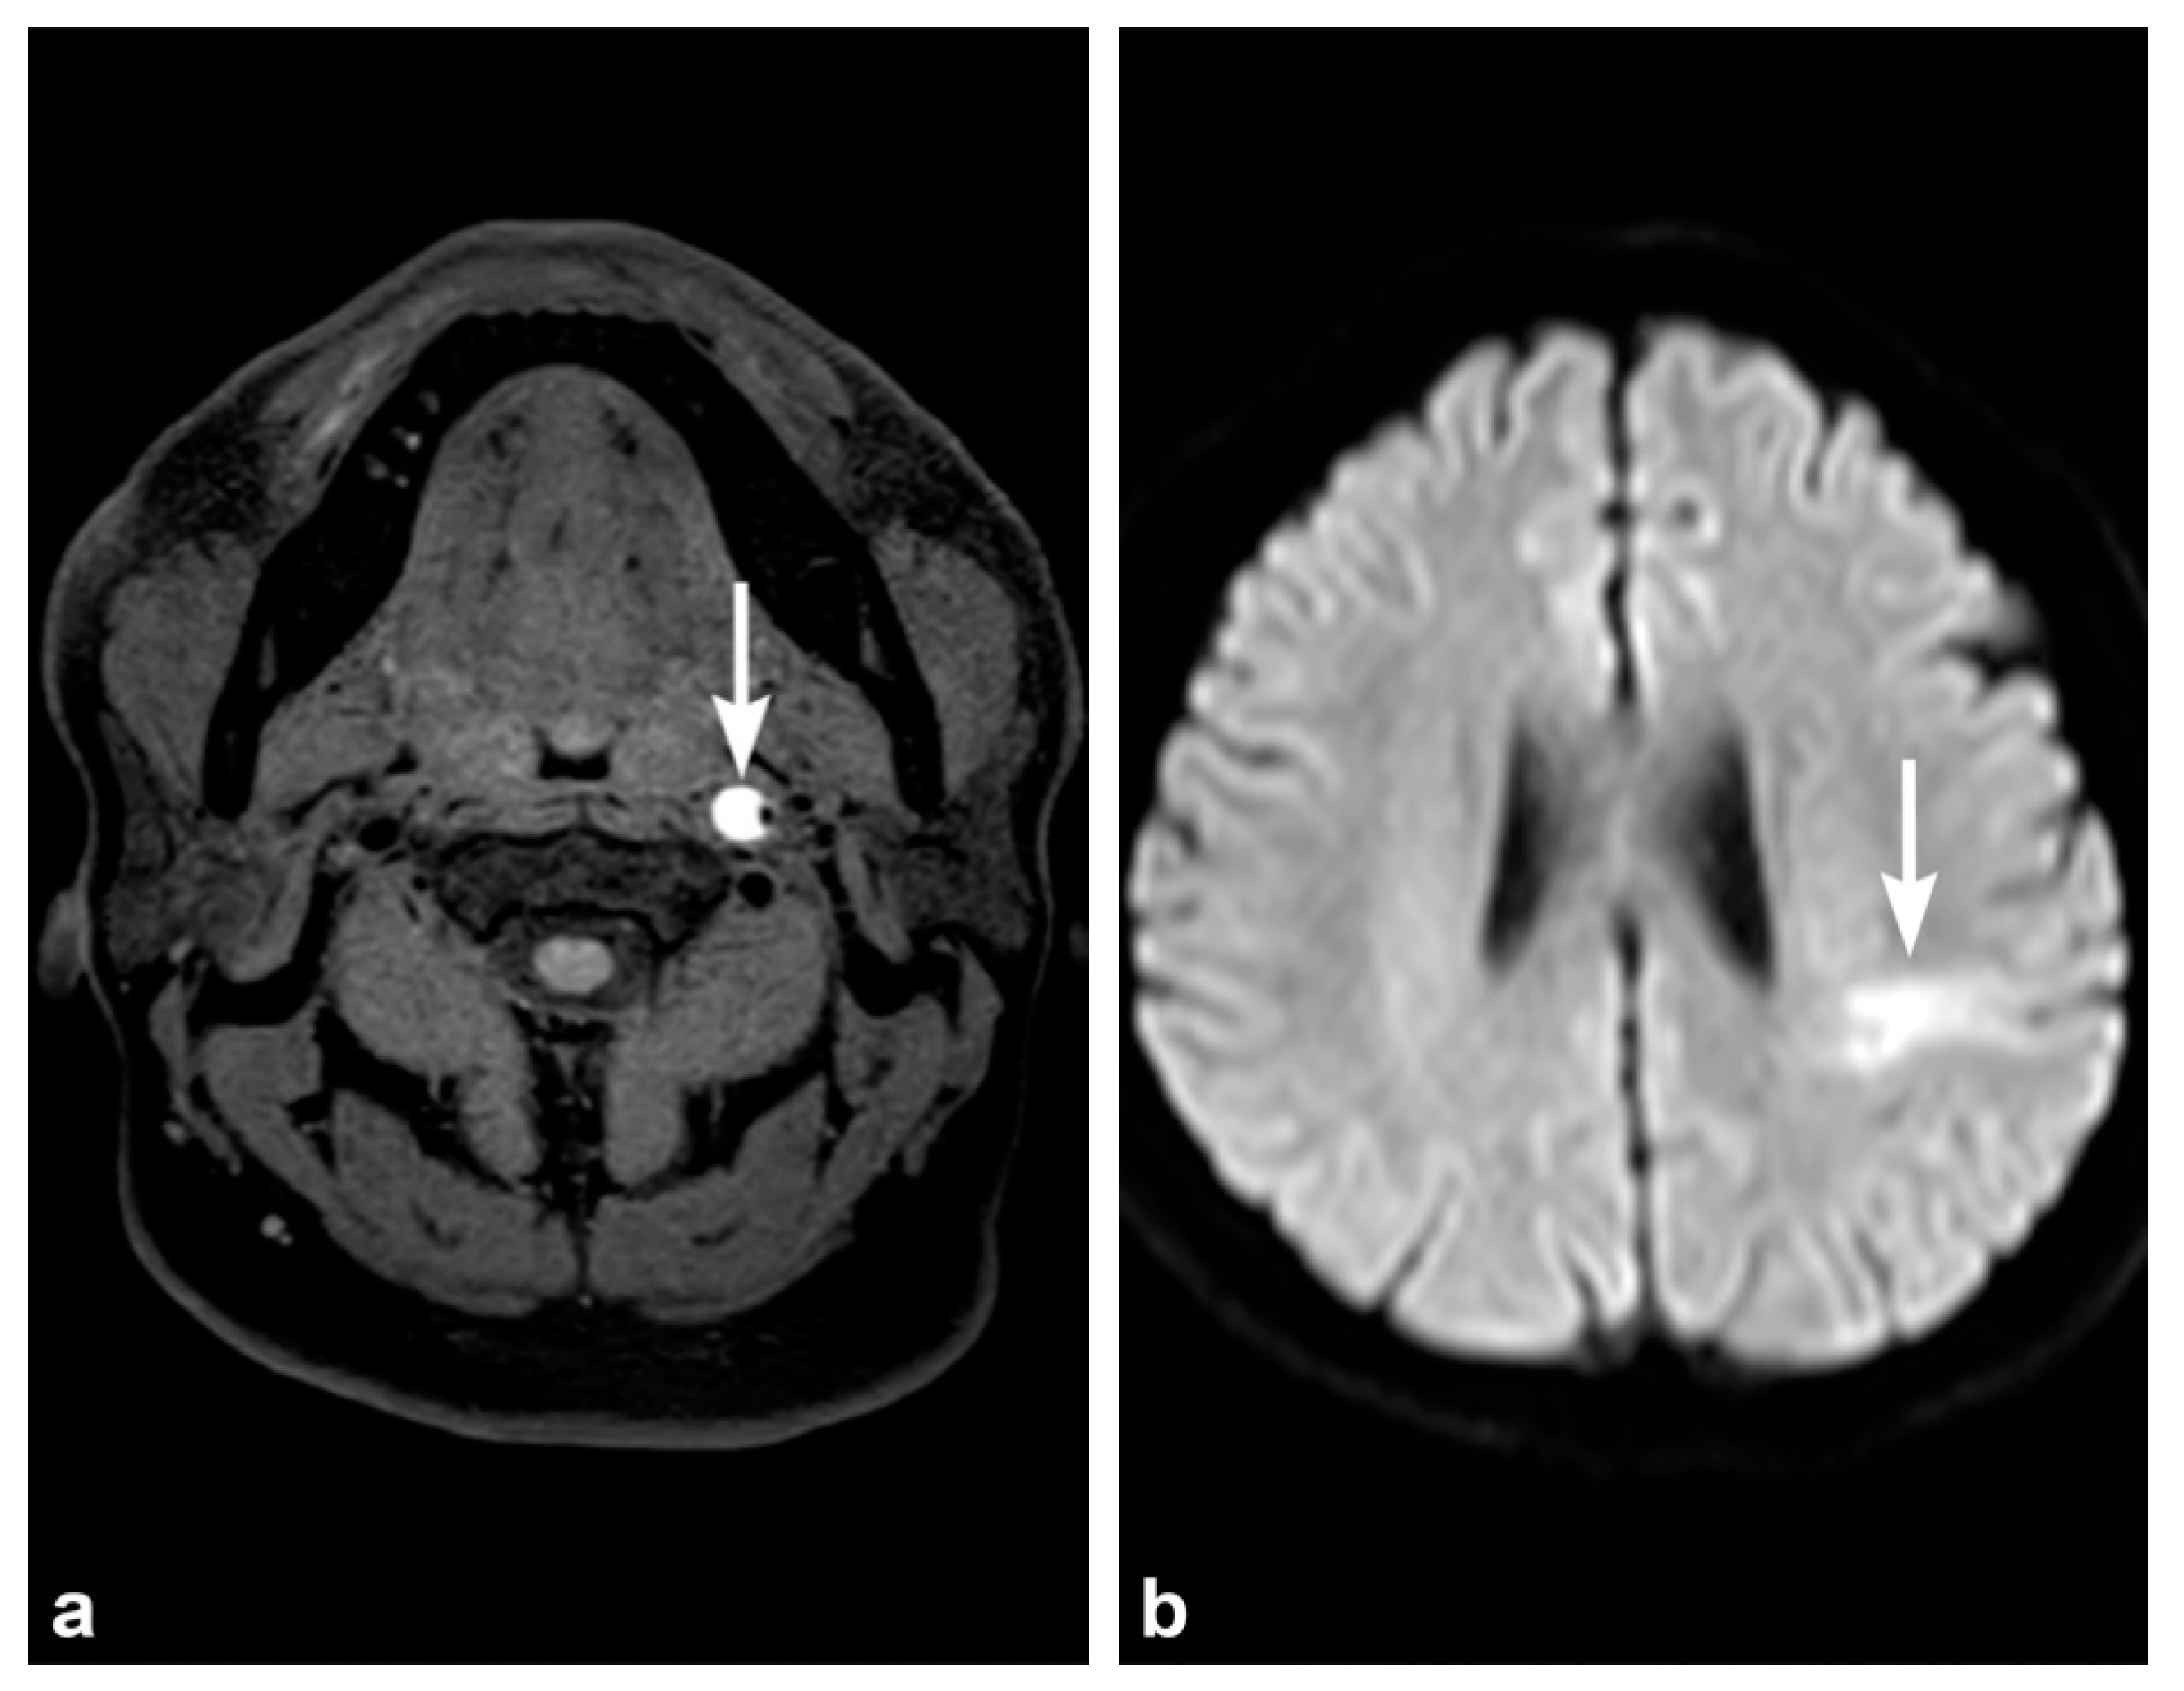

2. Imaging Techniques

3. Imaging Findings of Arterial Injury